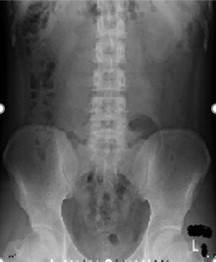

X線一般撮影

どんな検査?

放射線のひとつであるX線¹⁾を人体に照射し、各組織を通過してきたX線量の違いを画像として表示する検査です。一般撮影は放射線を利用した検査の中で最も基本となります。X線検査による被ばく²⁾は、全身被ばくではなく部分的な被ばくであり、可能な限り低い線量で検査が行われています。放射線治療など一部線量の大きい場合を除き、通常のX線検査では身体に影響を及ぼすことはありません。

何がわかるの?

体の中の骨や臓器の状態を最も手軽に画像情報として得ることができます。

■臓器の状態や位置

■体内の空気(肺や腸内ガスなどの体内ガス)